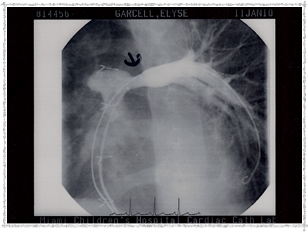

Catheterization 2003 - Balloon

Balloon picture